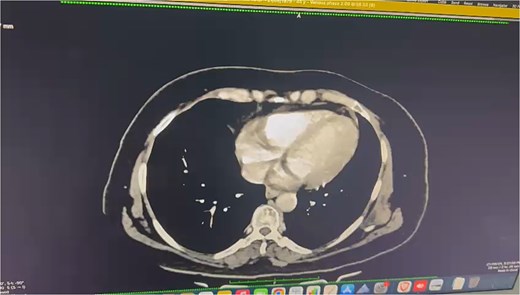

A provisional diagnosis of subacute intestinal obstruction likely secondary to an unusual etiology and further investigations were ordered. Contrast enhanced computed tomography (CECT) of the abdomen revealed short segments of symmetrically thickened walls in the proximal to mid-jejunal loop, accompanied by luminal narrowing, adjacent fat stranding, and mesenteric lymph nodes, raising suspicion of a neoplastic etiology (Fig. 1). An exploratory laparotomy was performed, during which a segment of the jejunum was resected for histopathological examination (Fig. 2).

Axial CECT image shows a short segment of asymmetric enhancing wall thickening involving the proximal to mid-jejunal loop (8 cm). There is luminal narrowing at the site of thickening, with adjacent fat stranding and mesenteric lymphadenopathy.